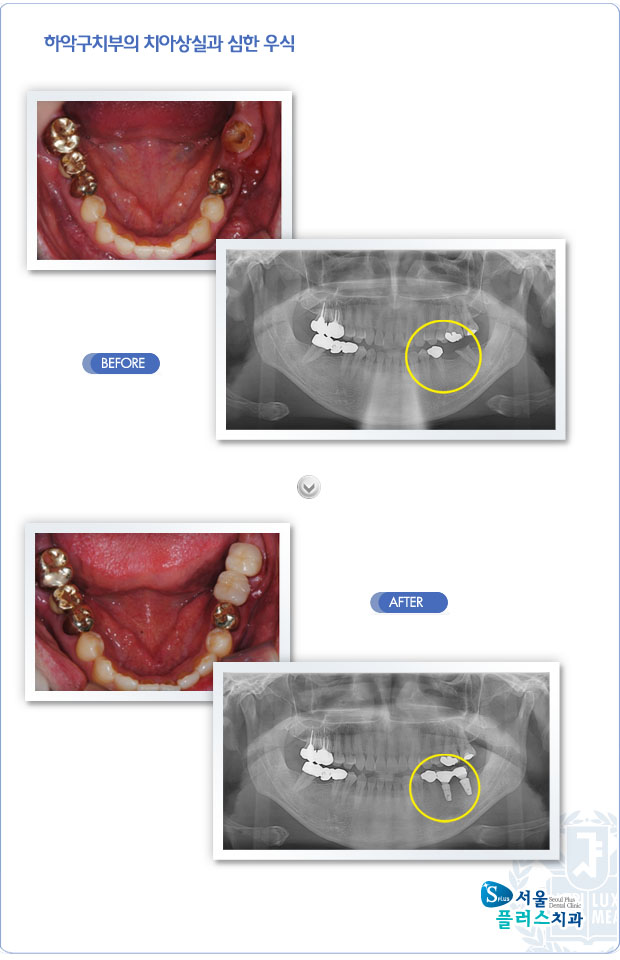

[임플란트] 하악구치부의 치아상실과 심한 우식